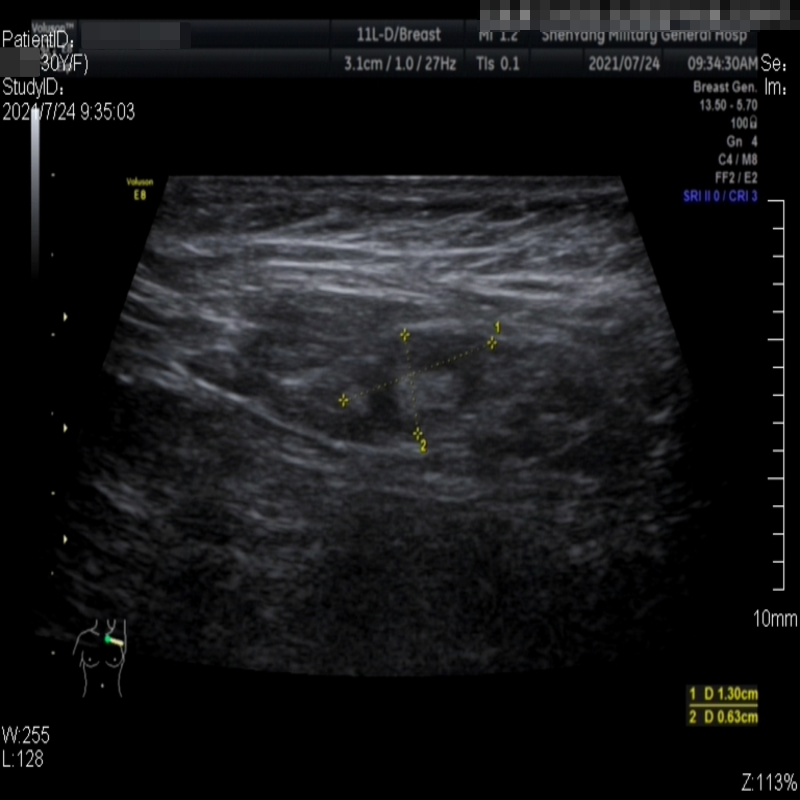

Images with certain annotations are considered noisy images in the context of the noise removal task, and corresponding images without these annotations are considered clean. Some typical images with various annotation are provided in Fig. 1.

In essence, a body marker annotation is a marker selected from a fixed set of icons that indicates different regions of the human body and its current orientation. It is typically located at the edge of the ultrasnoic image area and is labeled by the sonographer. On some ultrasound machines, the body marker annotation has a fixed position.

The radial line annotation is pairs of connected cross markers. They are usually placed at the edge of the lesion area, with its placement determined by the size of the lesion. One to three pairs of cross markers may be present in an image, corresponding to the three axes of 3D space, but typically there are only two pairs.

The vascular flow annotation is not an additional labeling feature meant to simplify identification. Rather, it serves as a bounding box that identifies the specific area of the image being examined by the ultrasound flowmeter. However, to keep things simple, we will continue to call it a form of annotation. The presence of this annotation indicates that the relevant examination has been conducted.

Refer to caption

(a)

(b)

(c)

Figure 1: Images with various annotations. (a) body marker annotation, (b) radical line annotation, (c) vascular flow annotation.